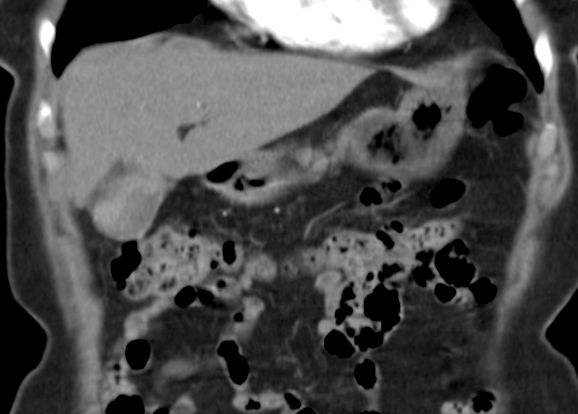

89-jährige Frau mit Infektzeichen. Zunächst sonographisch Verdacht auf Gallenblasenempyem. Im CT ein Gallenblasenkarzinom mit Leberinfiltration. Wegen Alter und AZ palliative Versorgung. | ||